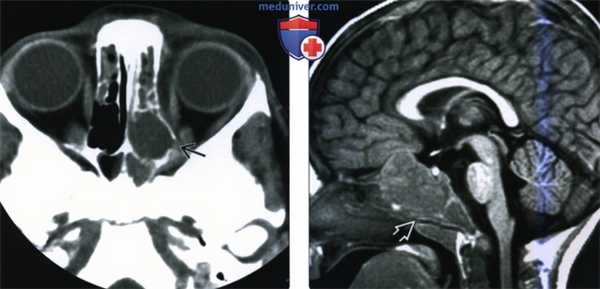

(Слева) При аксиальной КТ без КУ, выполненной ребенку с нейробластомой, визуализируется объемное образование в решетчатой кости. Определяется также небольшой участок эрозии костной ткани, наличие которого позволяет сделать вывод о метастазе нейробластомы.

(Справа) При сагиттальной МРТ Т1ВИ у двухлетнего ребенка с нейробластомой IV стадии в центре основания черепа визуализируется крупное объемное образование неоднородной структуры, минимально накапливающее контраст и оказывающее выраженное воздействие на скат. Лучевые признаки идентичны таковым для других злокачественных опухолей. Нейробластома чаще всего метастазирует в кости свода черепа или глазницы.